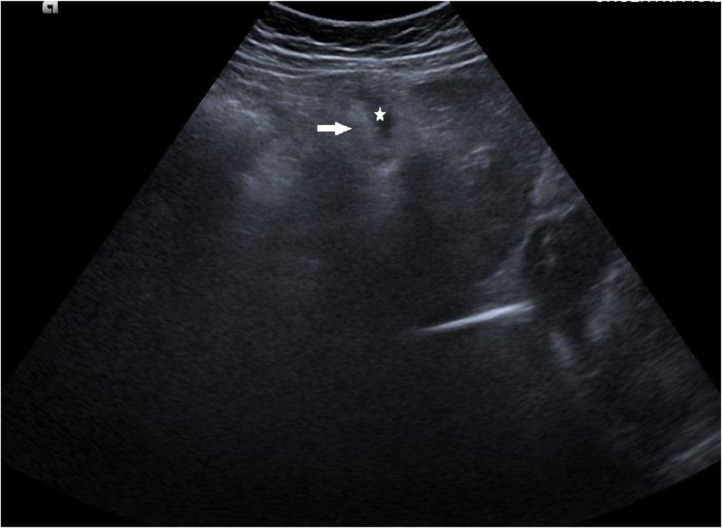

Fig. 4.

Follow-up abdominal ultrasound after therapy: a transverse scan in the epigastrium showed regression in the size of the falciform ligament (arrow) and abscess collection (star).